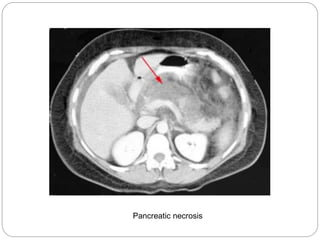

A common complication

of pancreatitis is the

development of

pancreatic necrosis.

Lack of gland

enhancement following

IV contrast

administration is

diagnostic. When over

half the pancreas

becomes necrosed,

the mortality rate may

reach as high as 30%.

Pancreatic necrosis